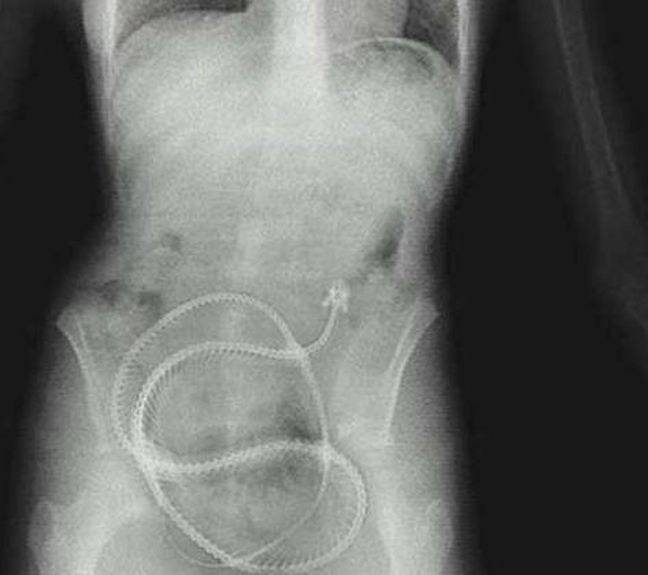

Δαχτυλίδι αρραβώνων Κλειδί Κουζινικά Χελι Μαγνητάκια Καρφιά 78 Κουτάλια και πιρούνια Φίδι

Ο,ΤΙ ΝΑ 'ΝΑΙ #φωτογραφίες Όταν μιλούν οι ακτινογραφίες! Αντικείμενα -και όχι μόνο- μέσα σε ανθρώπινα σώματα… 24·09·2013 13:33 16 σχόλια Δαχτυλίδι αρραβώνων Κλειδί Κουζινικά Χελι Μαγνητάκια Καρφιά 78 Κουτάλια και πιρούνια Φίδι